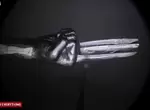

了解狀況之後,醫生就替患者進行了一場小手術,簡單來說就是在患者的手上切開一道小口,接著將筆芯取出就算完成,很輕鬆!整個過程都很順利,用夾子輕輕一夾筆芯就被拿出來了

接著將筆芯對著鏡頭展示一下,差不多約1公分左右的筆芯,夾出時可能稍微有動到,筆芯有稍微裂開一點,事後女醫生也不禁感嘆,這次真的是很不一樣的診治經驗,怎麼有人會讓筆芯待在自己的手裡這麼長時間呢?